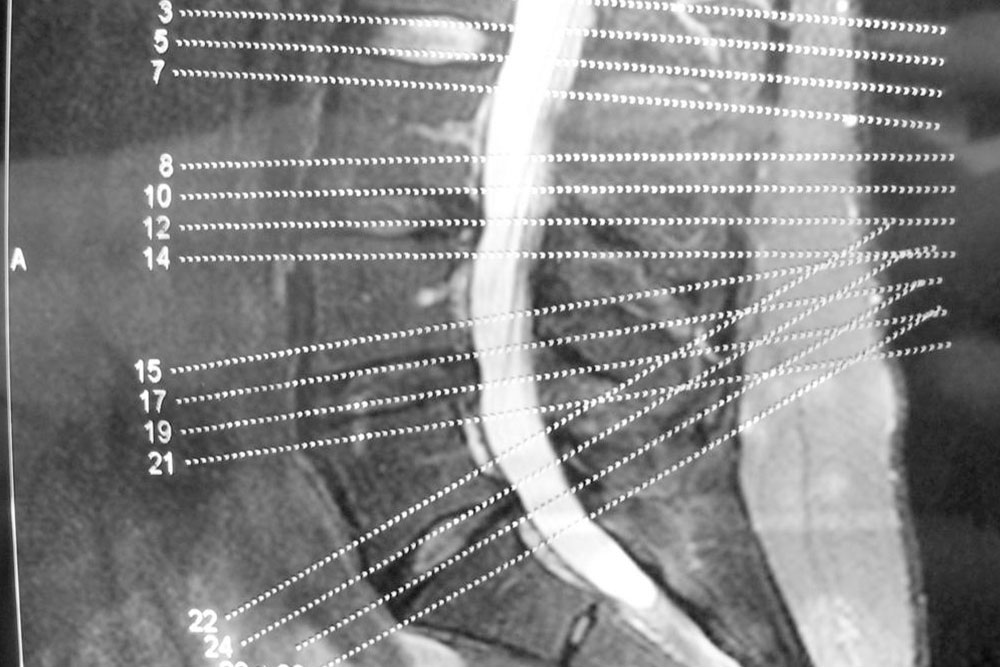

Degenerative Disc Disease

The spinal column consists of spinal discs that perform the task of providing padding between the vertebrae, i.e., the series of small bones that make up our backbone. They also act as shock absorbers and help the back remain flexible. As we age, these discs start gradually losing their elasticity property.

A common cause of this condition is the drying of your spinal discs. As you age, the water in the spinal discs dries out, flattening the spinal disc. A flattened spinal disc cannot absorb shock and they fail to provide padding to the vertebrae. Another cause of this disease can be a crack in the spinal disc. If the walls of the disc tear out, then there is a high chance that the soft core of the disc might push through the cracks and cause the disc to swell or, in the worst case, slip off.

Degenerative Joint Disease

Commonly referred to as Osteoarthritis, the degenerative joint disease is caused by the wearing of the body tissues. One of the most commonly affected areas is the joints in the spine.

This disease affects the facet joints, which are the joints that protect the vertebra in the spinal column from both sides. These joints make it possible for the spine to bend effortlessly.

The facet joints are lined with cartilages that cushion the joint and make sure that two adjacent vertebrae can glide smoothly against one another.

In degenerative joint disease, the cartilages break down, causing the adjacent joints to come in direct contact. When the joints rub against each other directly, it causes inflammation and unbearable pain.